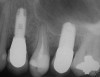

A 45-year-old female was referred for implant placement and prosthetic treatment in the area of tooth No. 24. The tooth had been extracted 4 years prior; the patient did not wear any denture thereafter. The radiograph revealed adequate bone height and a 5-mm to 6-mm ridge at the crest (Figure 2). It was decided to place a 11.5 mm in length, 3.75 mm in diameter Tapered Screw-Vent® implant (Zimmer Dental, www.zimmerdental.com) using the alveolar remodeling technique in the area of tooth No. 24.

Figure 2 Preoperative view of the area around tooth No. 24. On the left, a previously placed implant abutment

is visible.

Figure 4  Implant positioning; the radiograph taken 4 weeks after placement confirmed good primary stability.

Figure 2  Preoperative view of the area around tooth No. 24. On the left, a previously placed implant abutment is visible.

Figure 4